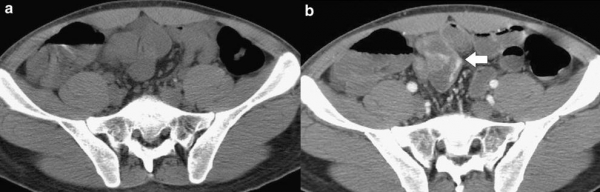

Hình 17: Hoại tử hồi tràng do chui vào thòng lòng được tạo bởi đầu tận cùng túi thừa Meckel dính với măt lưng mạc treo ở bệnh nhân nam 32 tuổi. A, CT quai ruột non dãn lớn, đoạn hồi – manh tràng xẹp nên nghi ngờ tắc ở hồi tràng. B, phẫu thuật: túi thừa Meckel và đoạn hồi tràng bị hoại tử. (Oguzhan KARATEPE. Cem DURAL et al (2008). Rare Complication of Meckel’s Diverticulum: Loop Formation of Diverticulum. Turk J Med Sci; 38 (1): 92.)